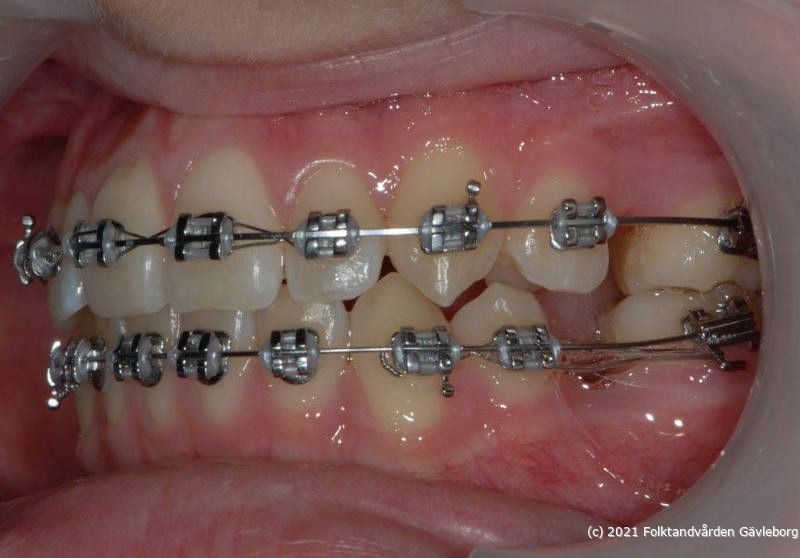

På ortodontiklinikerna diagnostiserar och behandlar vi bettfel på både barn och vuxna. Alla våra patienter kommer på remiss till oss. Vi behandlar bettfelen med fastsittande och avtagbar apparatur. Hos oss behandlas också de patienter som har avvikelser i käk- och ansiktsskelettet och som kräver tandreglering inför rekonstruktiv kirurgi. Vi har ett nära samarbete med allmäntandvård, privattandvård och övrig specialisttandvård i länet samt ett gott samarbete med Akademiska Sjukhuset i Uppsala när det gäller barn med olika syndrom och läpp-käk-gomdefekter. Våra specialistkliniker finns i Gävle och Hudiksvall.

Här nedan hittar du några exempel på vanligt förkommande behandlingar. Hittar du inget som passar det du vill visa, gå in på menyn ovan genom att föra musen över "Information". Navigera sedan till respektive apparatur. Klickar du på rubriken "Visa alla bilder" får du upp samtliga apparaturer som finns här.